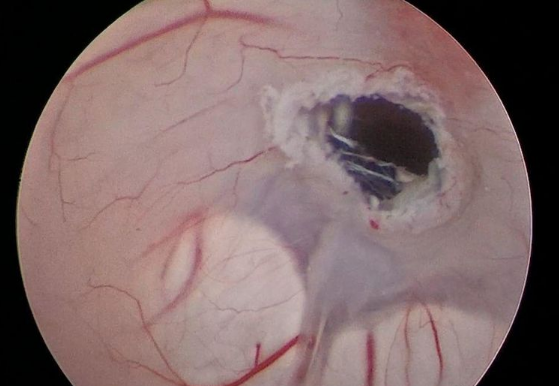

▲三脑室底造瘘术

在福建医科大学附属第一医院江常震教授的指导下,郭协力副院长、齐震主任、陈晓海副主任医师及蔡明发主治医师等人通力合作,于7月22日对王先生进行了微创神经内镜三脑室底造瘘术。手术利用脑室镜微创进入第三脑室,开放第三脑室底部约5mm,再造脑脊液循环通路,使脑室内积水得以流出。手术用时1个多小时就顺利完成,术后患者恢复到患病前状态,脑积水症状及影像均有不同程度的好转。